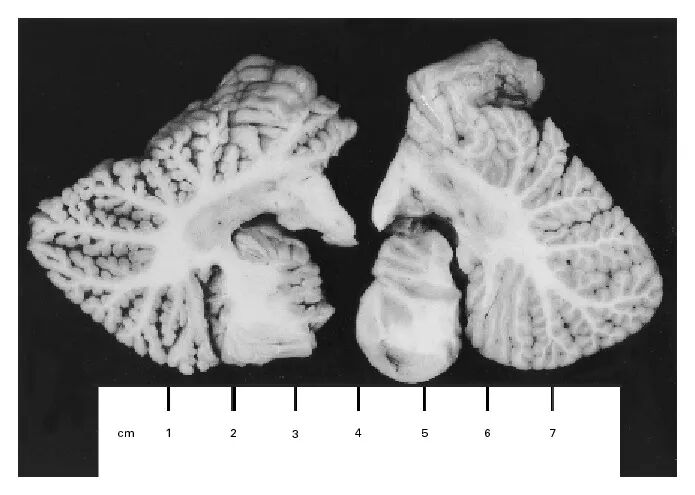

尸检结果发现,她的大脑皮层变薄到只有 3 毫米。距状裂(位于枕叶内侧)周围的视皮层、与听觉性语言功能有关的颞上回的上表面均严重胶质化。在大脑双侧半球初级视觉和听觉皮层中,出现了大量神经元丢失和神经胶质细胞增生。她的运动和感觉皮层也出现了类似情况。小脑弥漫性萎缩,其中颗粒细胞、浦肯野细胞、篮细胞均有广泛丢失,小脑表层的平行纤维也丢失了。

维特哈恩的小脑半球(左)与普通女性的小脑半球(右) 图片来源:NEJM 报告

在她的额叶和视皮层、肝脏、肾皮质中,汞含量极高。她的大脑汞含量是从未接触过汞的尸检样本的 600-1500 倍。